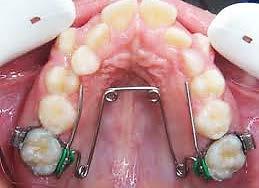

11, 12 y 13 mediante técnica CAD/ CAM, en su versión HT, color A2. Por otro lado, las otras 2 coronas de los OD 21 y 22 fueron confeccionadas con disco de zirconia Zahndent en tono A2. Estas fueron puestas a prueba mediante la aplicación Adobe Photoshop, con ayuda de una fotografía de las coronas tomada antes de su cementación definitiva, y una segunda medición con las coronas ya cementadas, únicamente se realizó el análisis en los OD 11 Y 21, los cuales fueron cementados con cemento translucido Multilink Speed de Ivoclar Vivadent, se tomaron fotografías con cámara profesional Cannon T8 y lente macro 100mm. Es importante mencionar que decidí utilizar cemento dual translucido para evitar alteración en el color de las coronas ya cementadas, con el fin de obtener mediciones puntuales de color y determinar las cantidades de pigmento que hay en cada corona mediante un fondo negro y así poder corroborar que se logró un buen mimetismo. El tiempo estimado para el procedimiento fue de 5 citas.

Figura 1. Coronas antes de su cementación (Francisco Javier Méndez Landa 2024).

porcentaje de 0 a 100, obteniendo el porcentaje exacto de cada uno de esos colores, que una vez mezclados obtenemos el tono real de las coronas (Figura 1).

Se realizó la medición del color de las coronas mediante una fotografía en formato RAW en fondo negro (Figura 2).